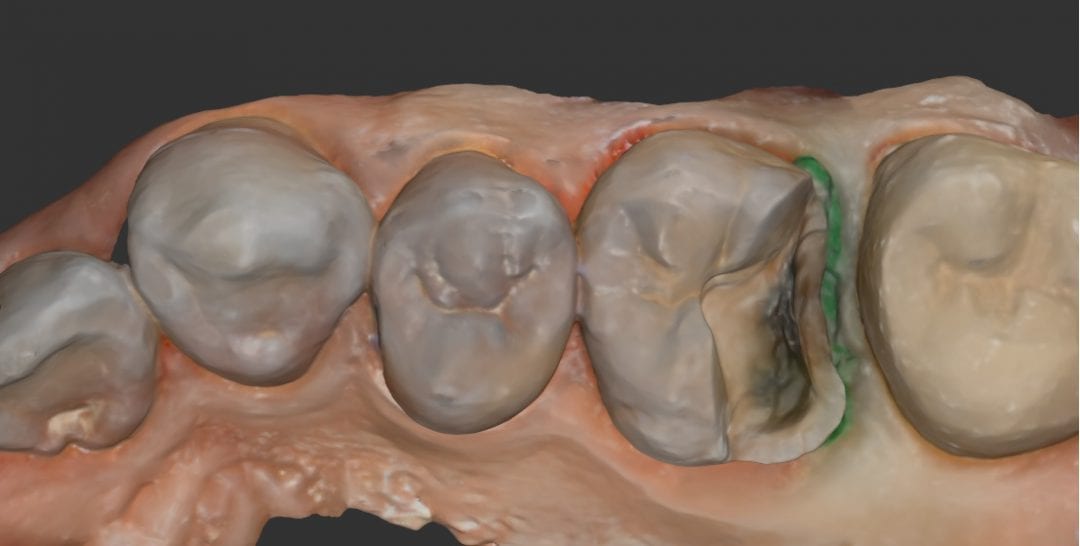

August 1, 2018In this particular clinical case, the patient has opted to utilize clear aligners to straighten some anterior crowding. The Medit i500 was used to capture both the upper and lower […]